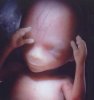

Что происходит на двенадцатой неделе беременности?

Длина плода от темени до крестца составляет около 61 мм. Вес малыша - около 9-13 г.

Основы организма уже заложены. Сейчас происходит развитие зачатков ногтей на пальцах рук и ног. Мышцы уже довольно развиты, но движения пока непроизвольные. Кишечник теперь не выходит за брюшную полость. На 12-ой неделе в нем возникают периодические сокращения, называемые перистальтическими. Под их действием происходит продвижение съеденной пищи. Печень малыша начинает выработку желчи, которая затем окажет помощь в переваривании пищевых жиров.

Если у Вас ожидается мальчик, то женские половые органы у плода на этом этапе выродились, оставив место мужскому началу. Плацента сейчас отвечает за производство прогестерона. На УЗИ можно увидеть, как малыш делает разные акробатические трюки. Ребенок с каждым новым днем все больше напоминает Вас. Теперь системы организма сформированы, впереди их рост и развитие.